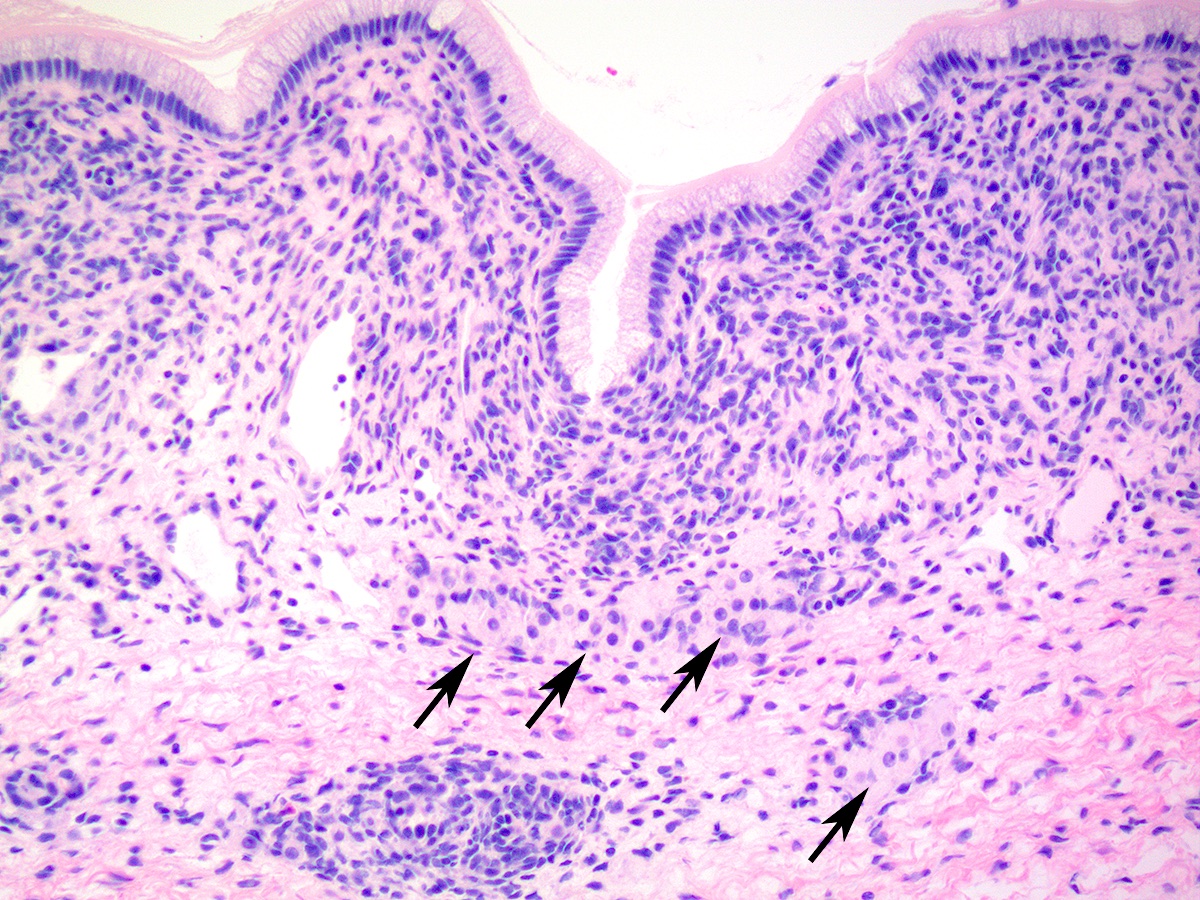

Microscopic (histologic) description

- Sertoli-Leydig cell tumor, retiform variant

- Approximately 15% of Sertoli-Leydig cell tumors demonstrate focal or diffuse retiform pattern, forming anastomosing, slit-like, irregular spaces or multicystic, sieve-like or papillary architecture (Am J Surg Pathol 1985;9:543, Am J Surg Pathol 1983;7:755)

Microscopic (histologic) images